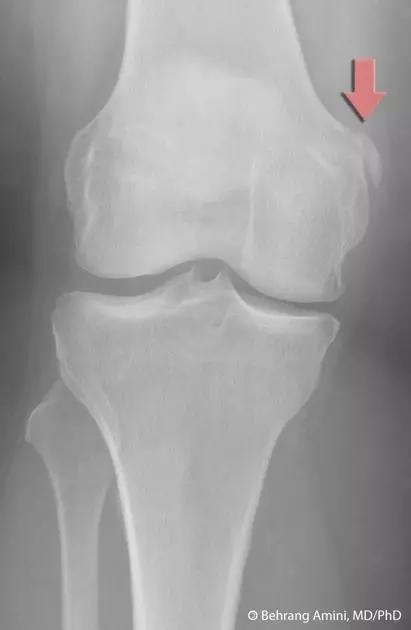

8. Segond 骨折和反向 Segond 骨折

(1)Segond 骨折

是发生在胫骨平台外侧的垂直撕脱性骨折。这种骨折在前后位 X 线片上显示最佳。屈曲位时膝关节受到内旋*力暴**作用,导致皮质骨撕脱性骨折,这种骨折常发生在运动员身上。

常引起股骨内髁和胫骨平台后内侧骨挫伤,75%~100% 的患者伴前交叉韧带断裂,33% 的患者伴外侧半月板损伤。

一位足球运动员的 Segond 骨折。A 正位片示关节线下方胫骨外侧皮质撕脱(箭头)。B MRI 冠状位 T1 加权像示附着于髂胫带的骨折碎片(空箭头)(来源:Radiol Clin N Am 53 (2015) 737–755,YU,Ohio)